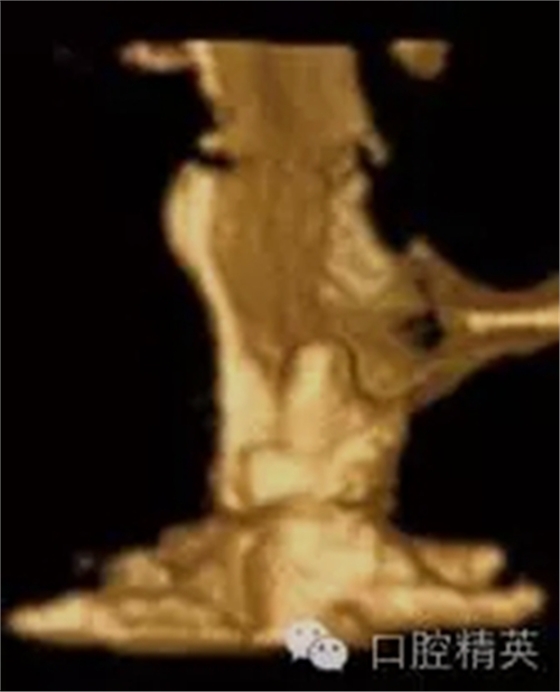

圖1c:術(shù)后用ICATCBCT進(jìn)行三維立體效果再現(xiàn),顯示種植體穿入上頜竇的實(shí)踐情況

近年來(lái),椎體束CT(CBCT)的應(yīng)用已經(jīng)逐漸滲透于口腔學(xué)的各個(gè)領(lǐng)域,它為顱頜疾患的治療檢查增加了一個(gè)維度,從而拓展了我們的視野。以CBCT為基礎(chǔ)的牙科成像技術(shù)獲取三維數(shù)據(jù),通過(guò)整合加工,重建沒(méi)有變形,放大,沒(méi)有解剖結(jié)構(gòu)重疊的立體影像。